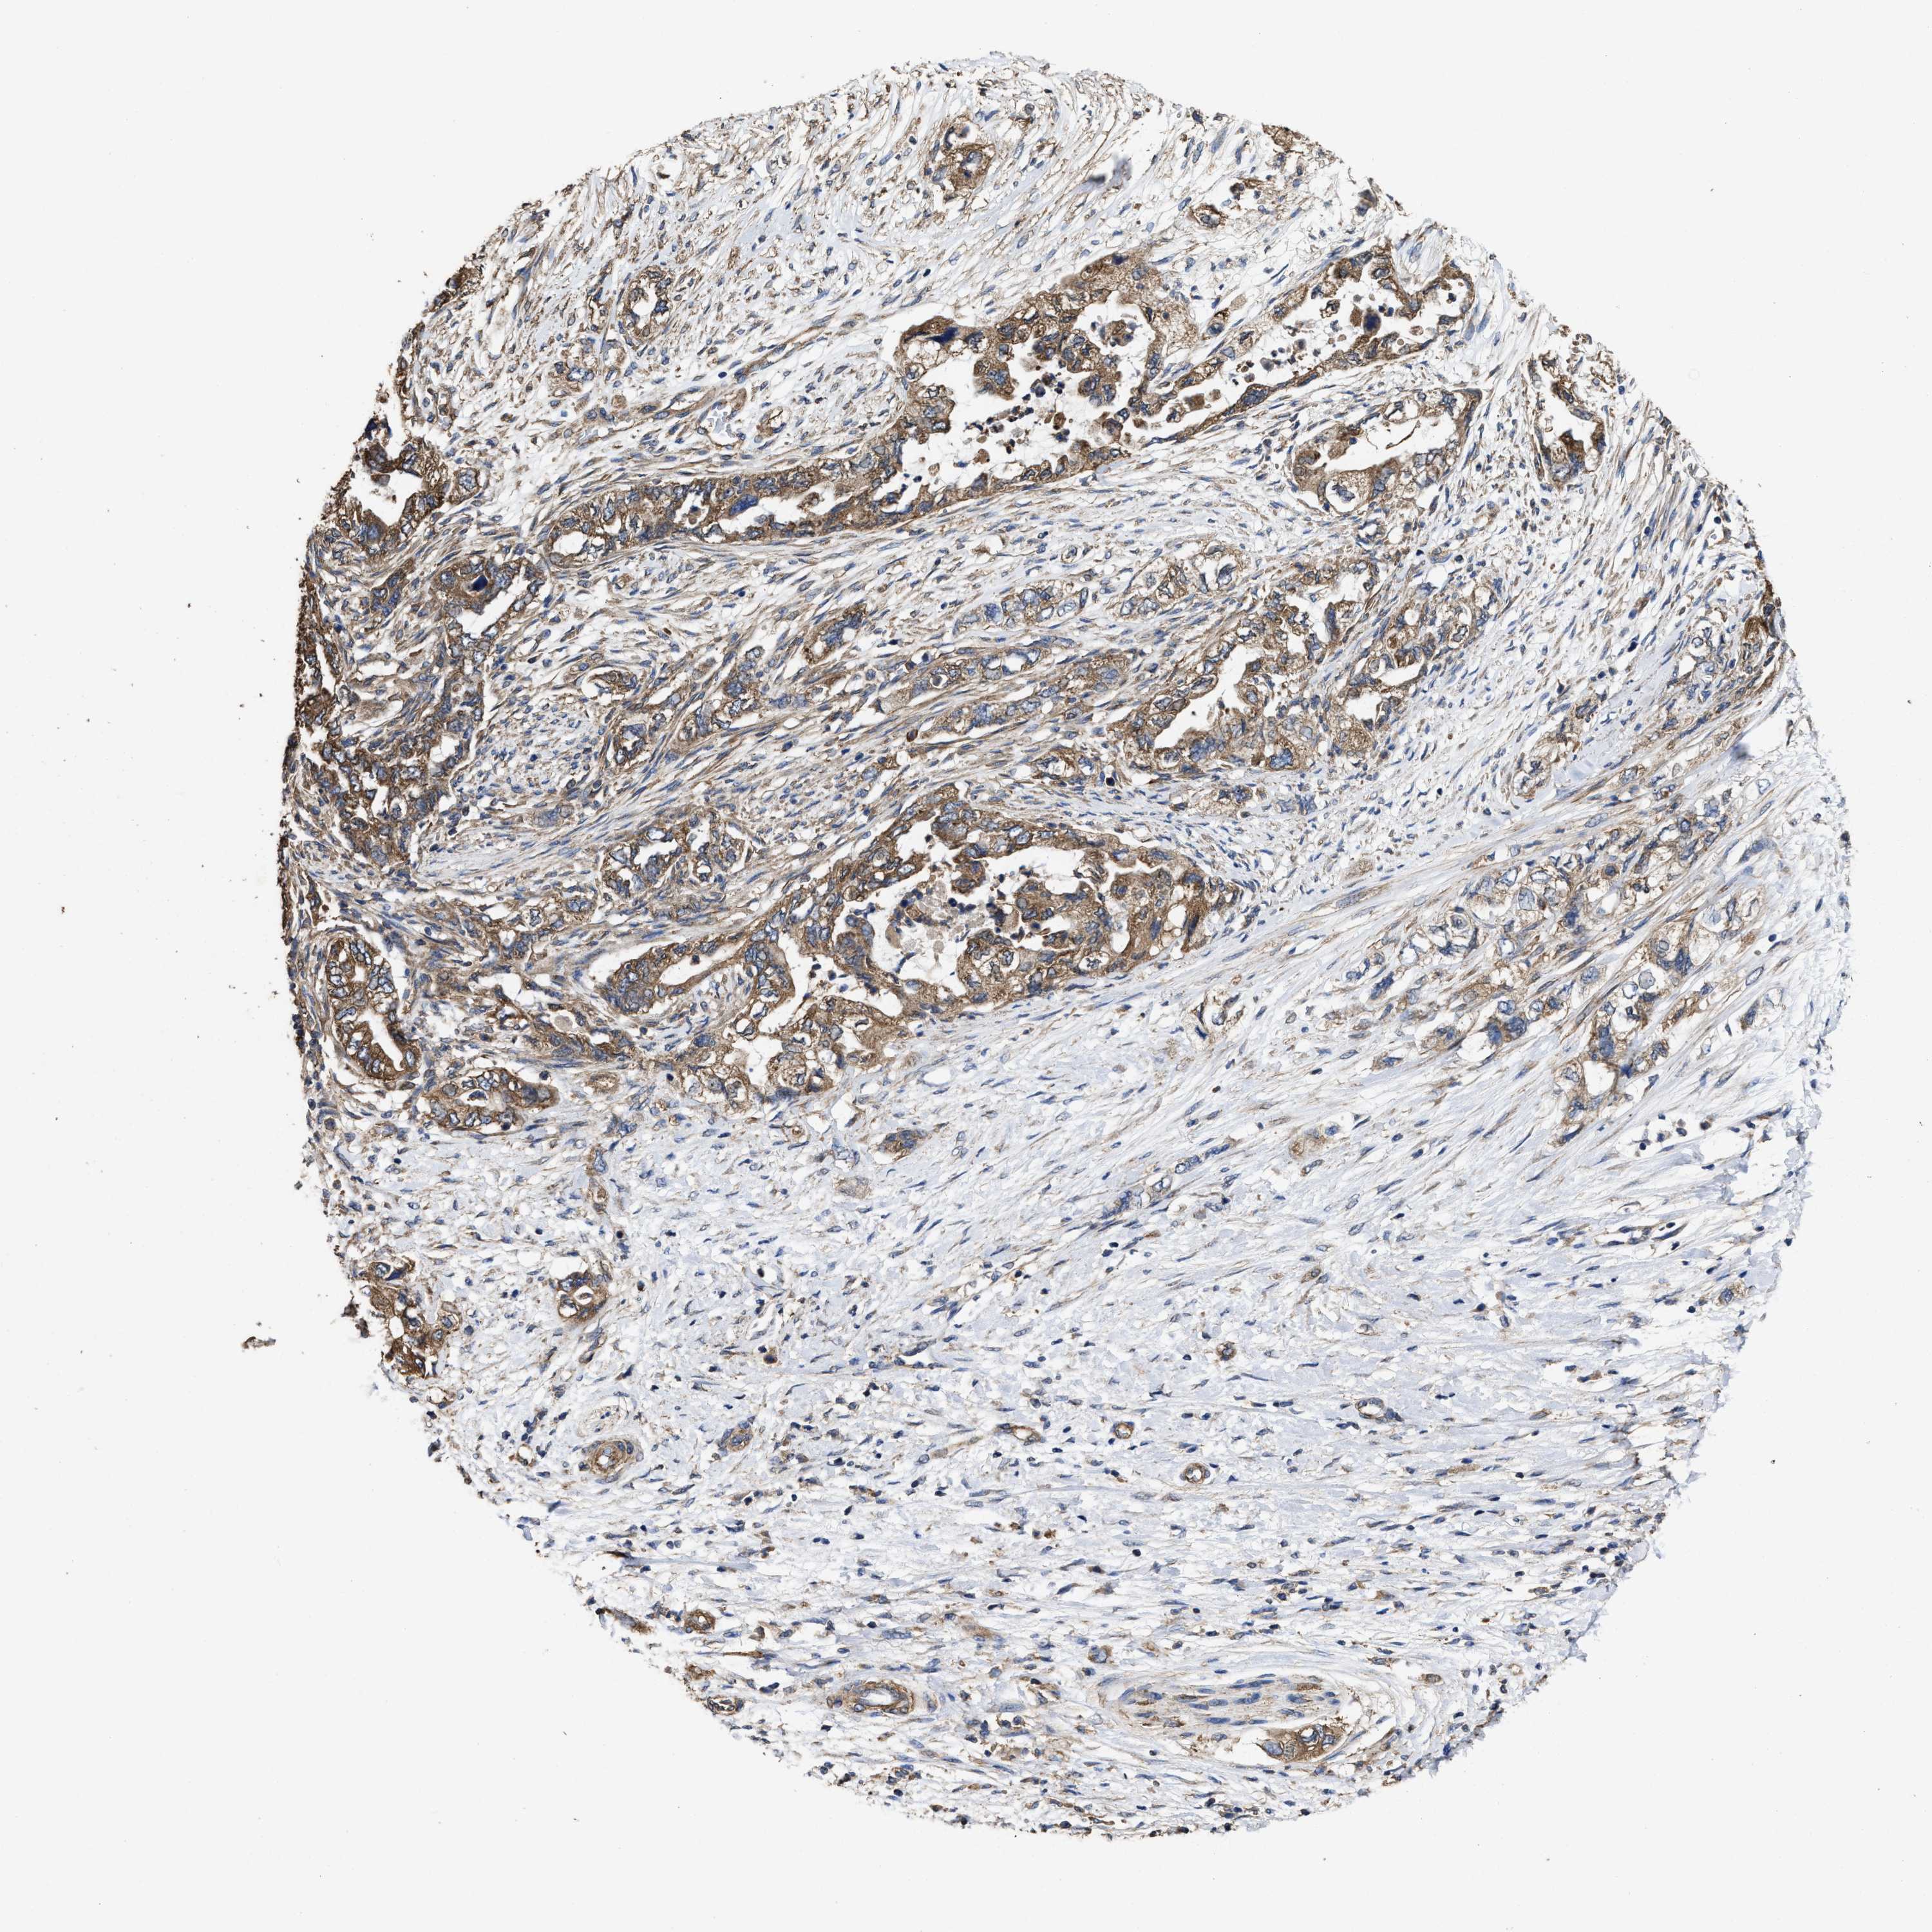

PANCREATIC CANCER - Protein expressioni

A mouse-over function shows sample information and annotation data. Click on an image to view it in a full screen mode. Samples can be filtered based on level of antibody staining by selecting one or several of the following categories: high, medium, low and not detected. The assay and annotation is described here.

Note that samples used for immunohistochemistry by the Human Protein Atlas do not correspond to samples in the TCGA dataset.

Antibody stainingi

Antibody staining in the annotated cell types in the current human tissue is reported as not detected, low, medium, or high, based on conventional immunohistochemistry profiling in selected tissues. This score is based on the combination of the staining intensity and fraction of stained cells.

Each image is clickable and will lead to virtual microscopy that enables deeper exploration of all samples and also displays staining intensity scores, fraction scores and subcellular localization as well as patient and tissue information for each sample.

Antibody HPA020872

Staining

High

Medium

Low

Not detected

Intensity

Strong

Moderate

Weak

Negative

Quantity

>75%

75%-25%

<25%

None

Location

Nuclear

Cytoplasmic/membranous

Cytoplasmic/membranous,nuclear

Adenocarcinoma, NOS